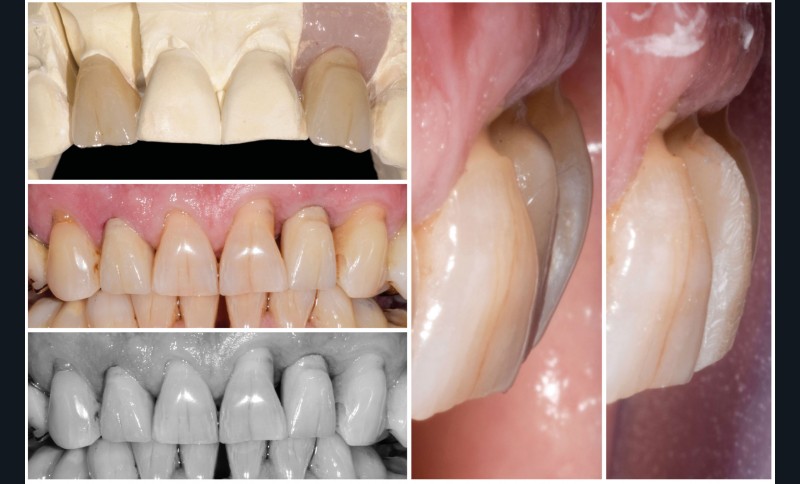

La proposition thérapeutique retenue par le patient est donc une réhabilitation par couronne céramique sur 12 (dento-portée) et 22 (implanto-portée). Ce choix thérapeutique impose de concevoir des dents qui s’intègrent au mieux dans l’harmonie du sourire, tout en étant conscient des limites d’un tel traitement.